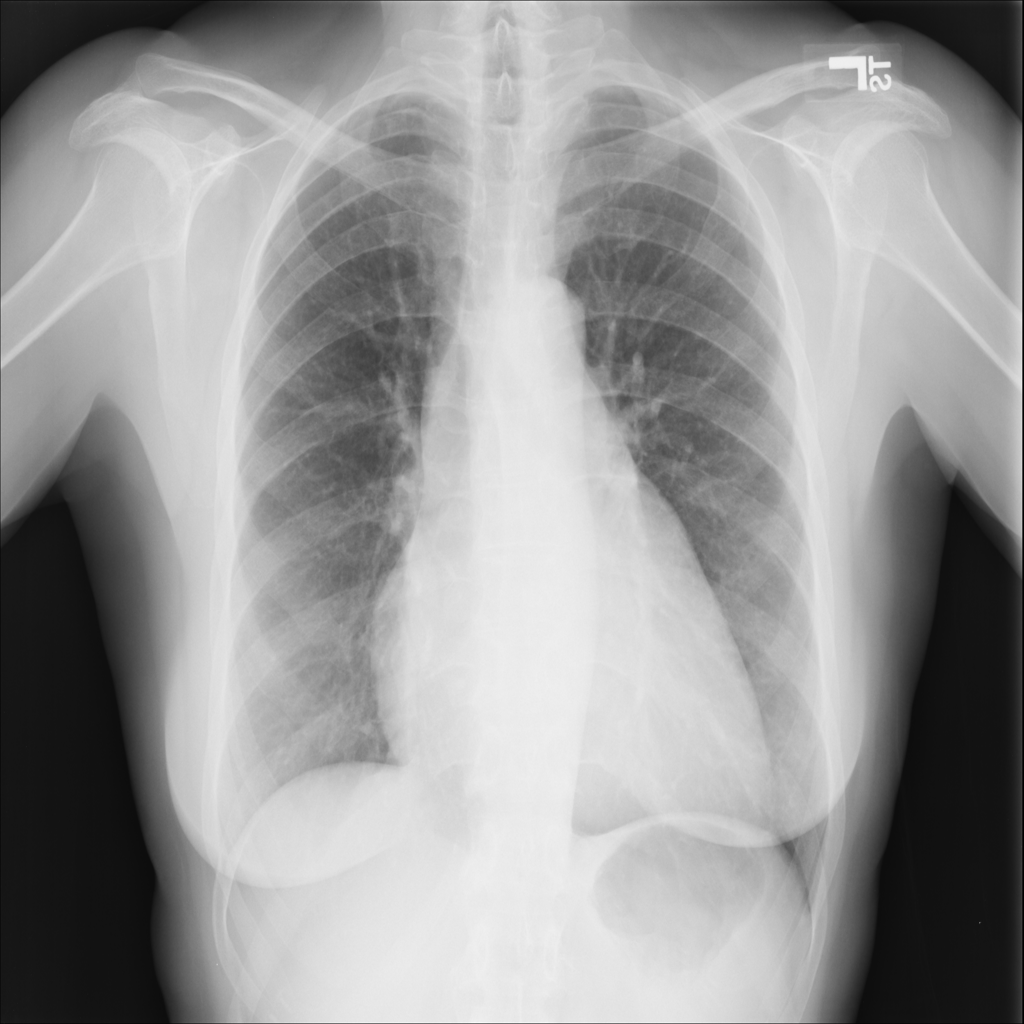

PAT-E36C · IMG-000Cardiomegaly

PAT-E36C · IMG-000

PA